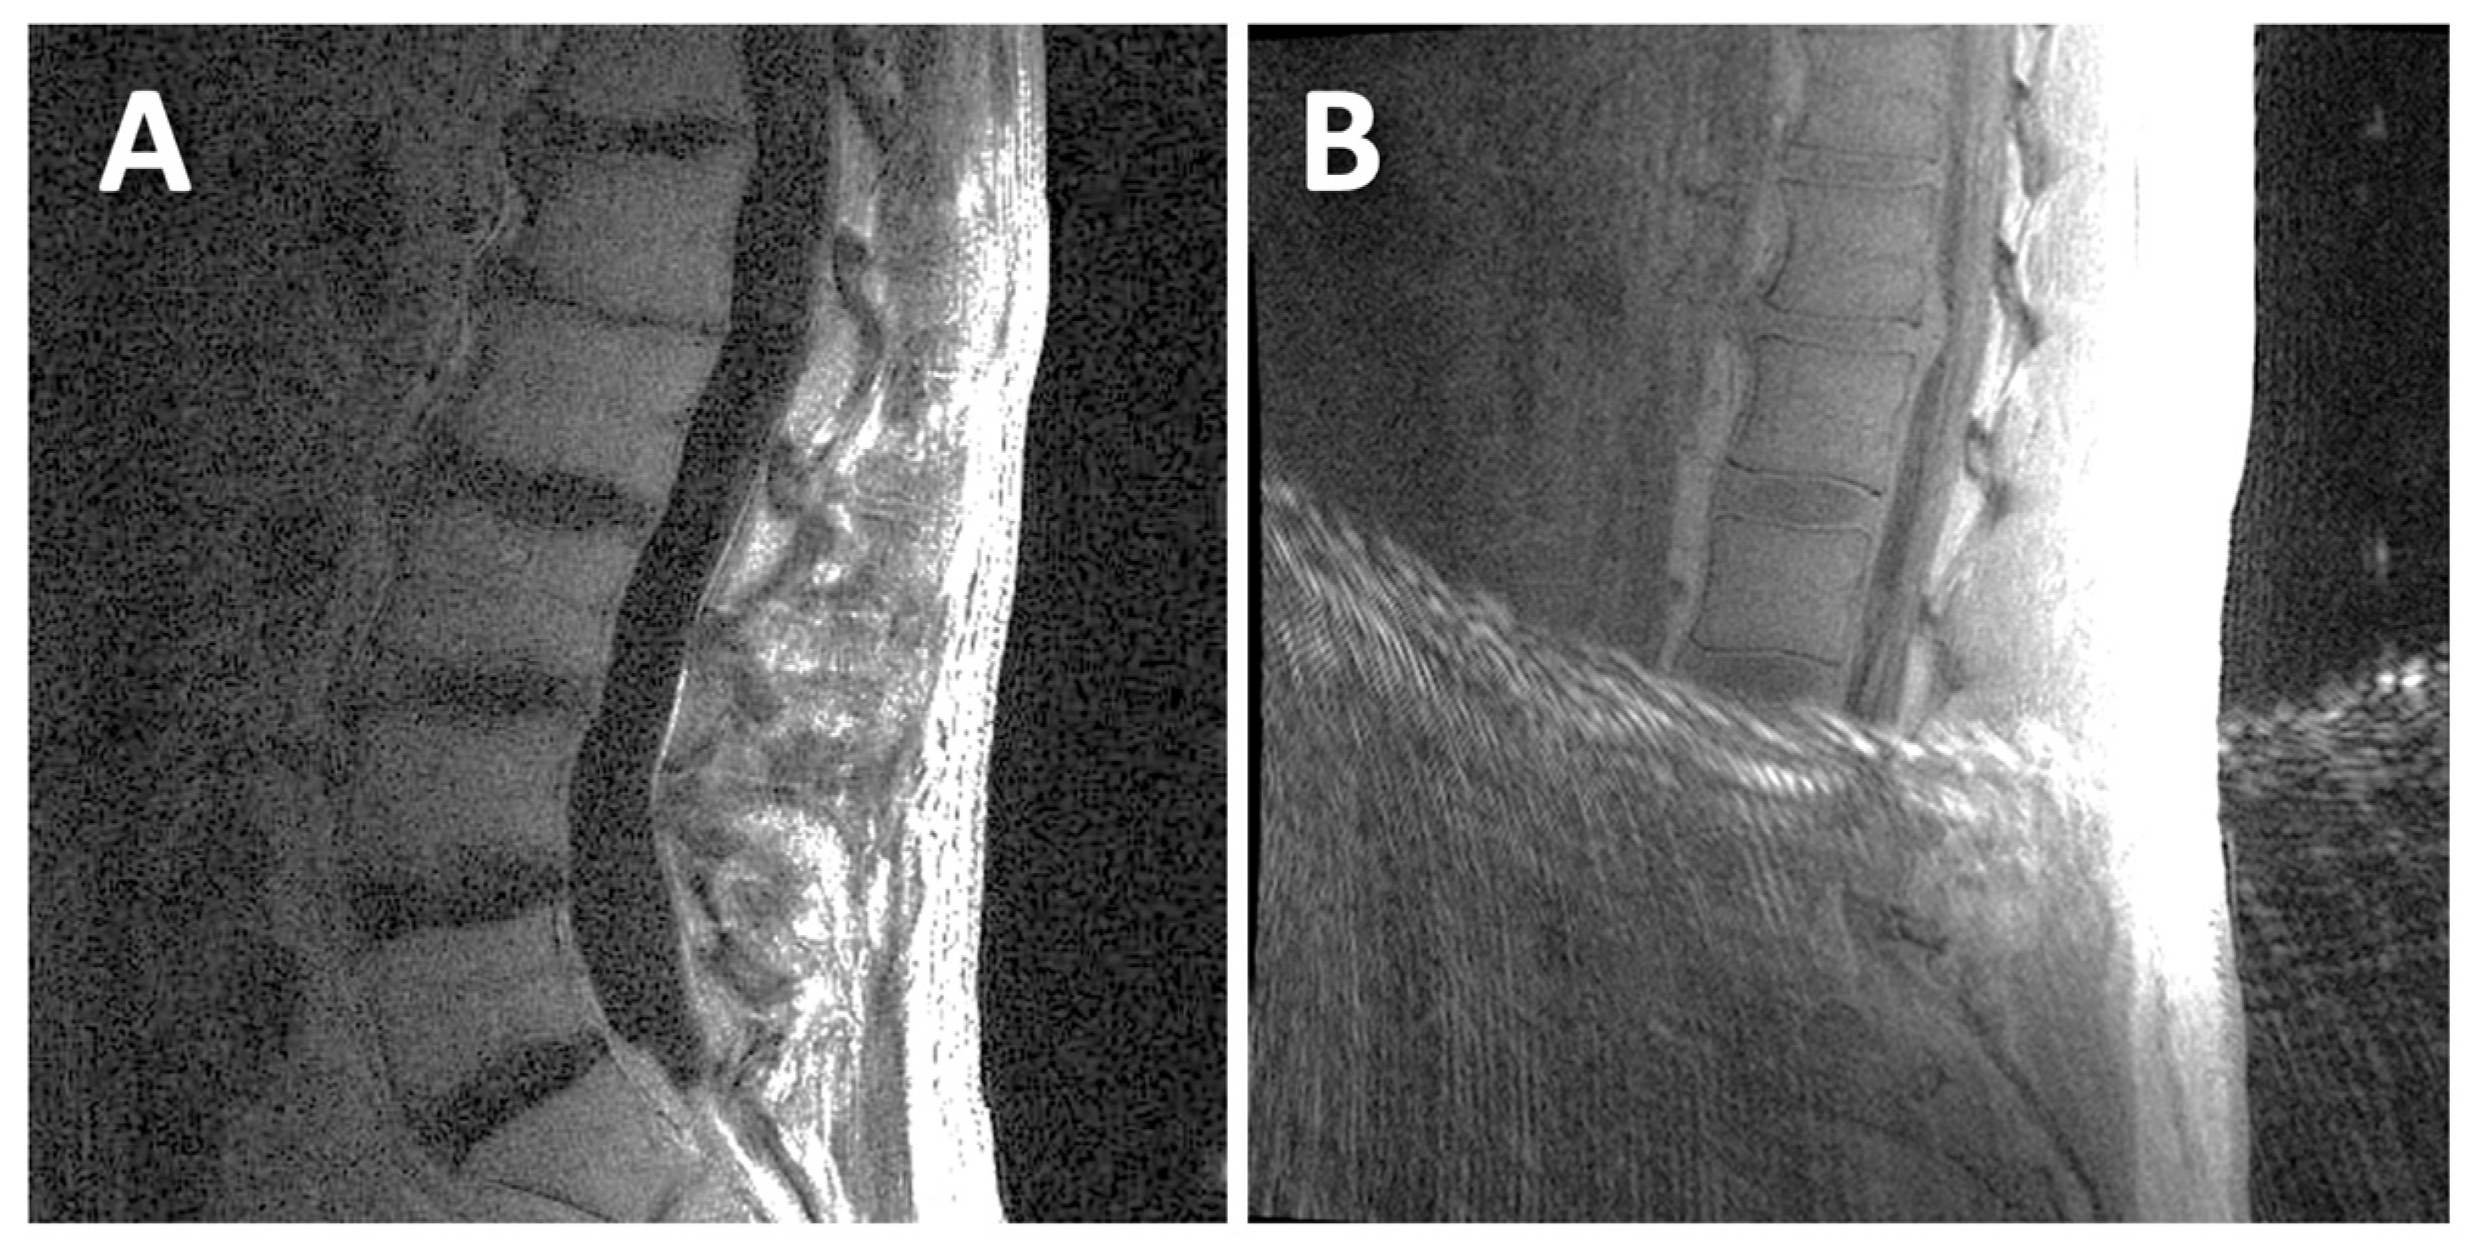

| DVJ | G0 | G1 | G2 |

|---|---|---|---|

| Asx | 93.8% | 2.5% | 3.8% |

| Sx | 56.8% | 12.4% | 30.7% |